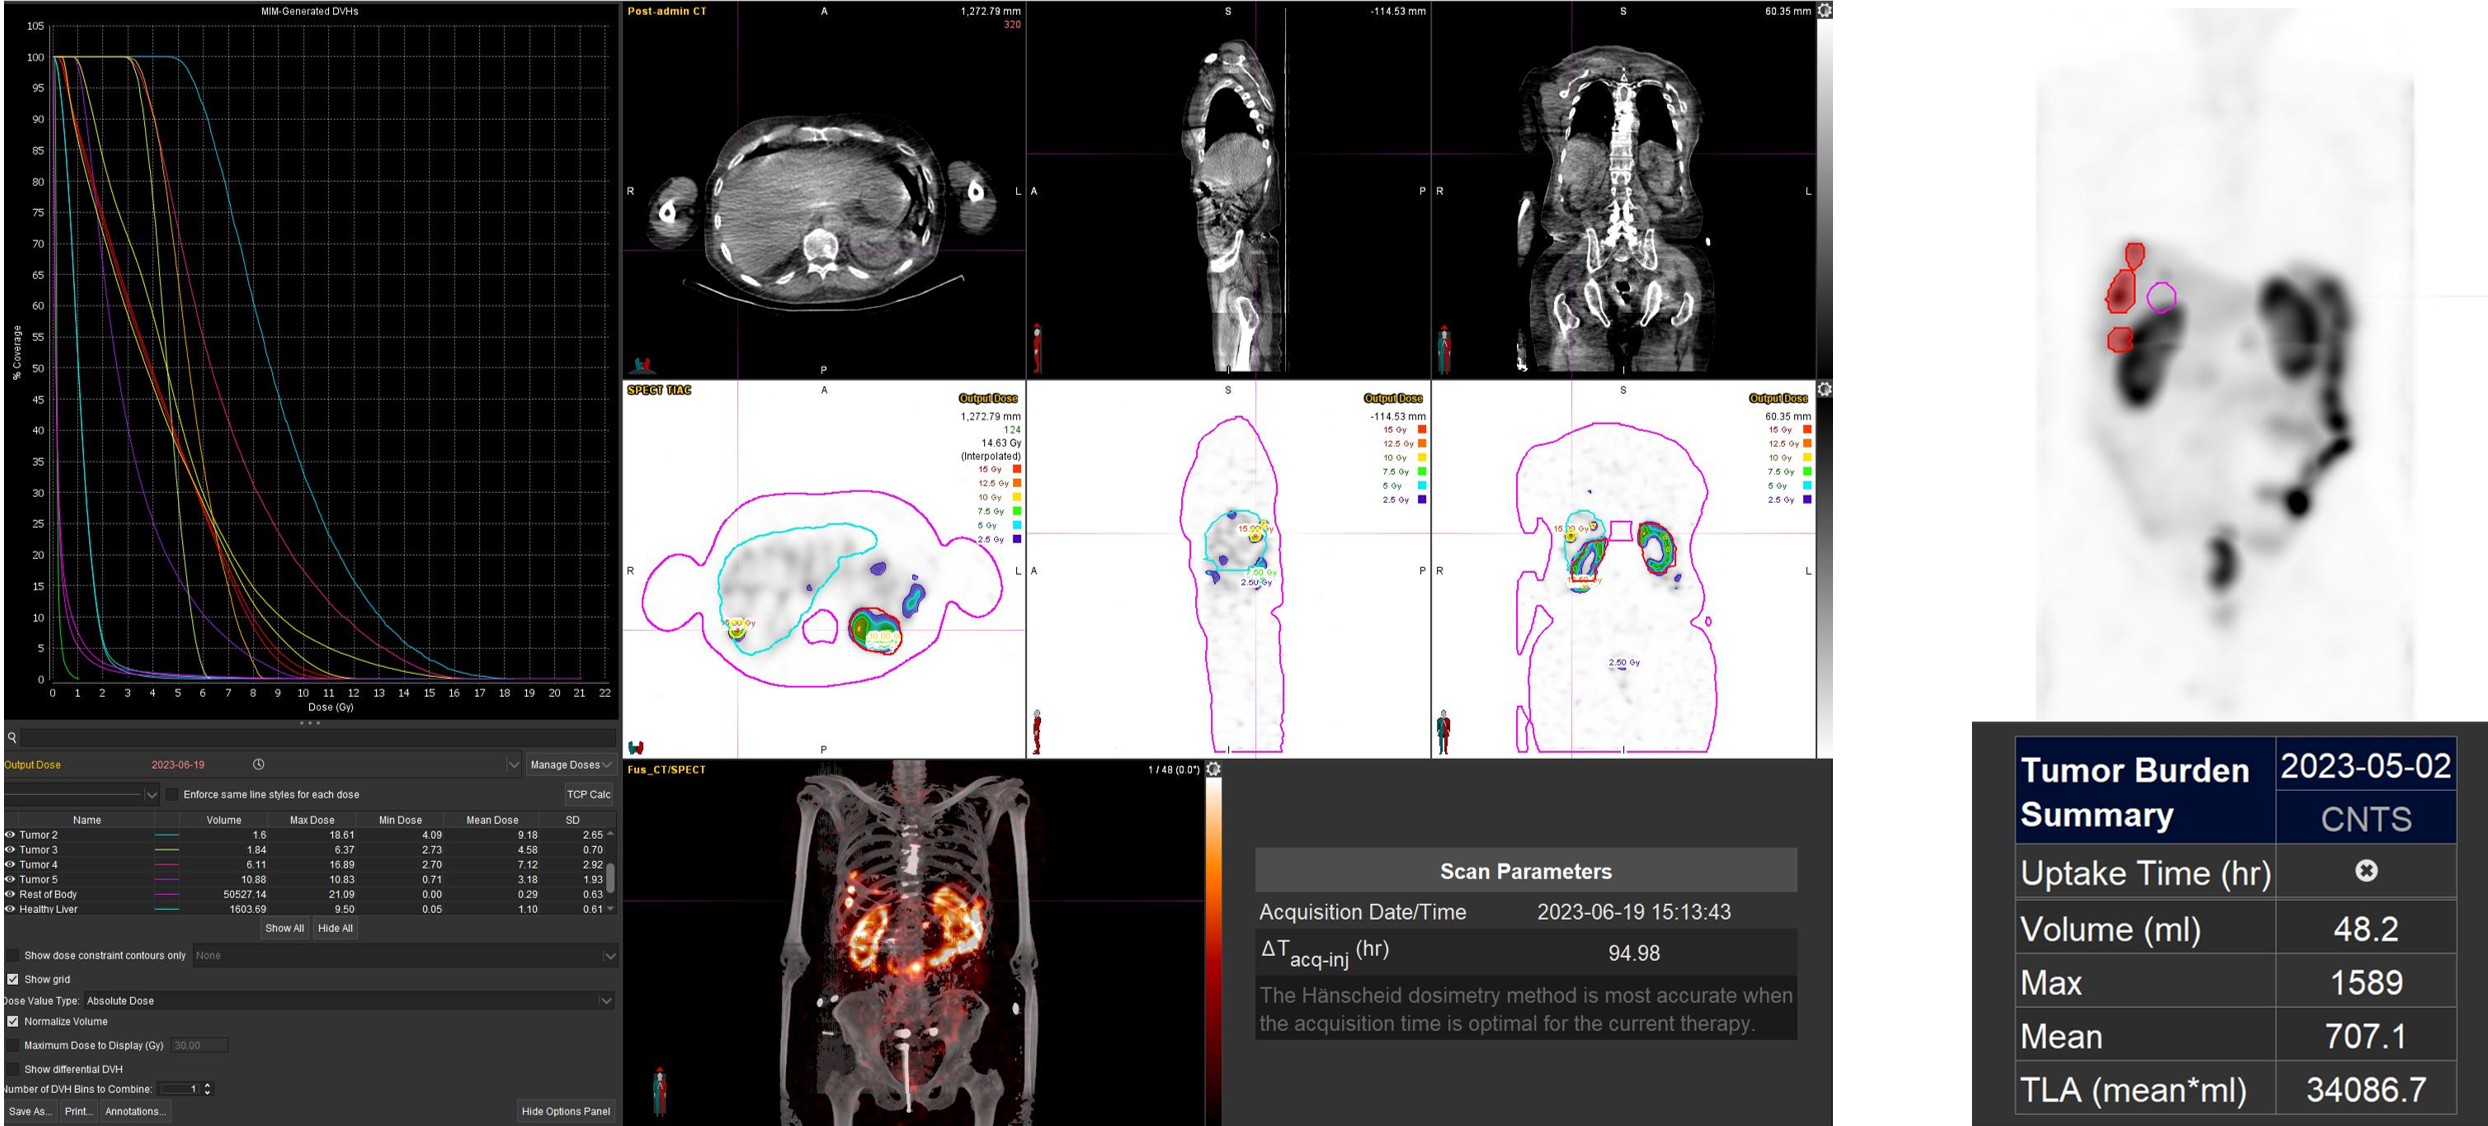

Η θεραπεία με Lu-177 DOTATATE (PRRT – Peptide Receptor Radionuclide Therapy) αποτελεί μια από τις πλέον εξελιγμένες μορφές στοχευμένης ραδιονουκλιδικής θεραπείας για νευροενδοκρινείς όγκους του γαστρεντερικού και του παγκρέατος, αξιοποιώντας την υπερέκφραση των υποδοχέων σωματοστατίνης στους νεοπλασματικούς ιστούς. Η διαδικασία περιλαμβάνει τον ακριβή προσδιορισμό της έκτασης της νόσου μέσω Ga68 DOTATATE PET/CT, την επιβεβαίωση υψηλής έκφρασης υποδοχέων SSTR και στη συνέχεια τη χορήγηση του Λουτέσιο-177 DOTATATE, το οποίο δεσμεύεται εκλεκτικά στους ανωτέρω υποδοχείς. Η ενέργεια του β-εκπομπού Λουτέσιου επιτρέπει στοχευμένη κυτταροτοξική δράση μέσα στον όγκο, με ελάχιστη διασπορά σε υγιείς ιστούς. Η σύγχρονη πρακτική ενσωματώνει ειδικά λογισμικά δοσιμετρίας, που υπολογίζουν την απορροφούμενη δόση σε κρίσιμα όργανα (ήπαρ, νεφροί, μυελός) και την πραγματική δόση στον όγκο, επιτρέποντας εξατομικευμένο σχεδιασμό και βελτιστοποιημένη θεραπευτική στρατηγική. Μετά από κάθε κύκλο θεραπείας πραγματοποιείται απεικονιστικός έλεγχος, αξιολόγηση τοξικοτήτων και συνολική εκτίμηση ανταπόκρισης, καθοδηγώντας τις επόμενες φάσεις της θεραπείας. Το Lu-177 DOTATATE έχει αποδειχθεί εξαιρετικά αποτελεσματικό στη σταθεροποίηση και συχνά στη συρρίκνωση της νόσου, παρατείνοντας την επιβίωση και βελτιώνοντας σημαντικά την ποιότητα ζωής των ασθενών.

Η αξία της μεταθεραπευτικής δοσιμετρίας

Με τη SPECT‑CT ποσοτικοποίηση υπολογίζουμε απορροφούμενες δόσεις σε όγκους και όργανα‑στόχους (νεφροί, σιελογόνοι, ήπαρ, μυελός κ.ά.). Αυτό:

Σημείωση: Σύμφωνα με πρόσφατες κλινικές εργασίες/σειρές ασθενών – όπως οι LUMEN‑2 (για ΝΕΤ) και νεότερες μελέτες σε PSMA‑στόχο – η ποσοτική δοσιμετρία συσχετίζεται με την έκβαση και βελτιώνει τον θεραπευτικό σχεδιασμό.